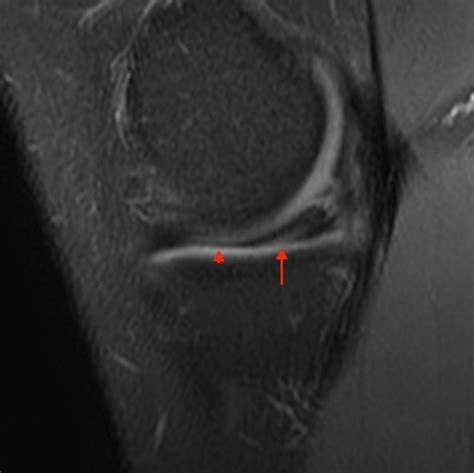

A Bucket Handle Injury is a specific type of meniscal tear that occurs in the knee. The meniscus is a C-shaped piece of cartilage that acts as a shock absorber between the thighbone (femur) and the shinbone (tibia). When a tear occurs in a way that the inner portion of the meniscus flips up into the joint, it is called a bucket handle tear because it resembles the handle of a bucket.

• MRI (Magnetic Resonance Imaging): To provide detailed images of the soft tissues, including the meniscus, to confirm the diagnosis.